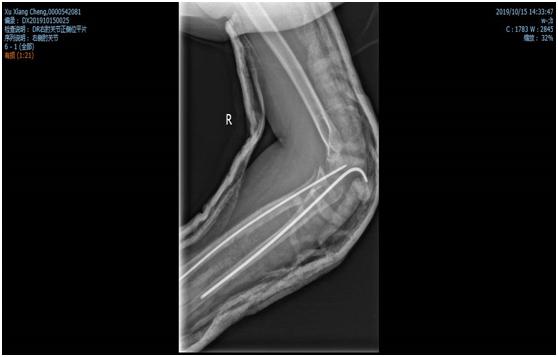

锁骨干骨折术前照片

锁骨干骨折术后照片

闭合穿针是采用手法复位技术,应用克氏针内固定,配合石膏外固定,治疗常见四肢骨折,优势明显,具有恢复快,美观、不残留畸形,不需二次手术等特点。 相对于钢板内固定需广泛剥离骨膜破坏血运,骨折愈合慢,术后不能尽早持重(负重),二次手术取钢板等问题。闭合穿针不破坏骨折端血运,骨折愈合快,使患者早期投入到生产生活中。适用于各类四肢骨折,如上肢:锁骨骨折、肱骨外科颈骨折、肱骨干骨折、前臂各种尺桡骨骨折等。下肢:股骨干骨折、胫腓骨骨折,踝关节骨折、跟骨骨折等。